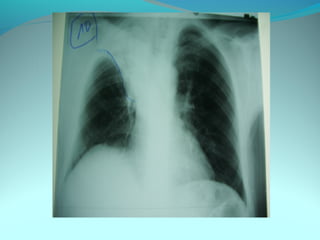

Opacité triangulaire a base cardiaque a sommet

axillaire dense et homogène

Par ailleurs on note

Une opacité plus dense que celle arrondie de 3cm de

diam hilaire gauche ;une surélévation de la coupole

diaphragmatique gauche é poche a aire gastrique

DIAGNOSTIC :

ADP hilaire gauche avec trouble de ventilation

Surelevation de la coupole G et de la poche gastrique

avec de clarté le médiastin

DIAGNOSTIC:

Hernie diaphragmatique paralysie du diaphragme